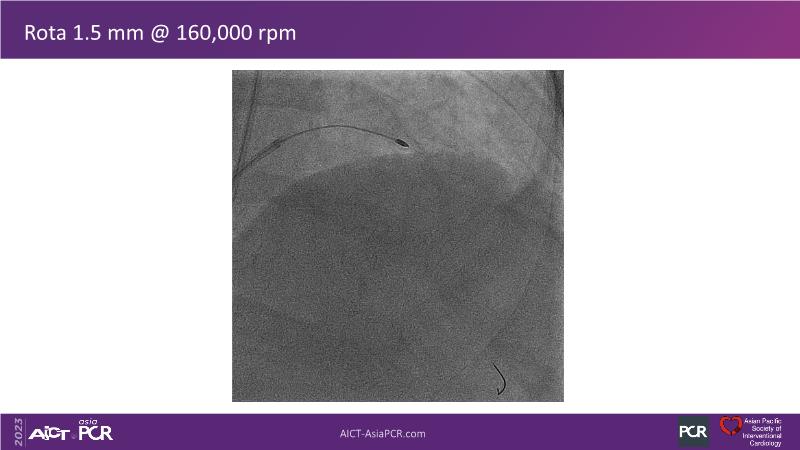

This session is recommended for you if you are seeking insights into the advantages of using IVUS imaging over visual assessment for better outcomes in left main bifurcation procedures. Discuss with experts the benefits of using RotaCUT in lesion preparation for left main bifurcation and explore the impact of high radial strength stents on the procedure's success.

• To see advantages of RotaCUT as part of lesion preparation in left main bifurcation